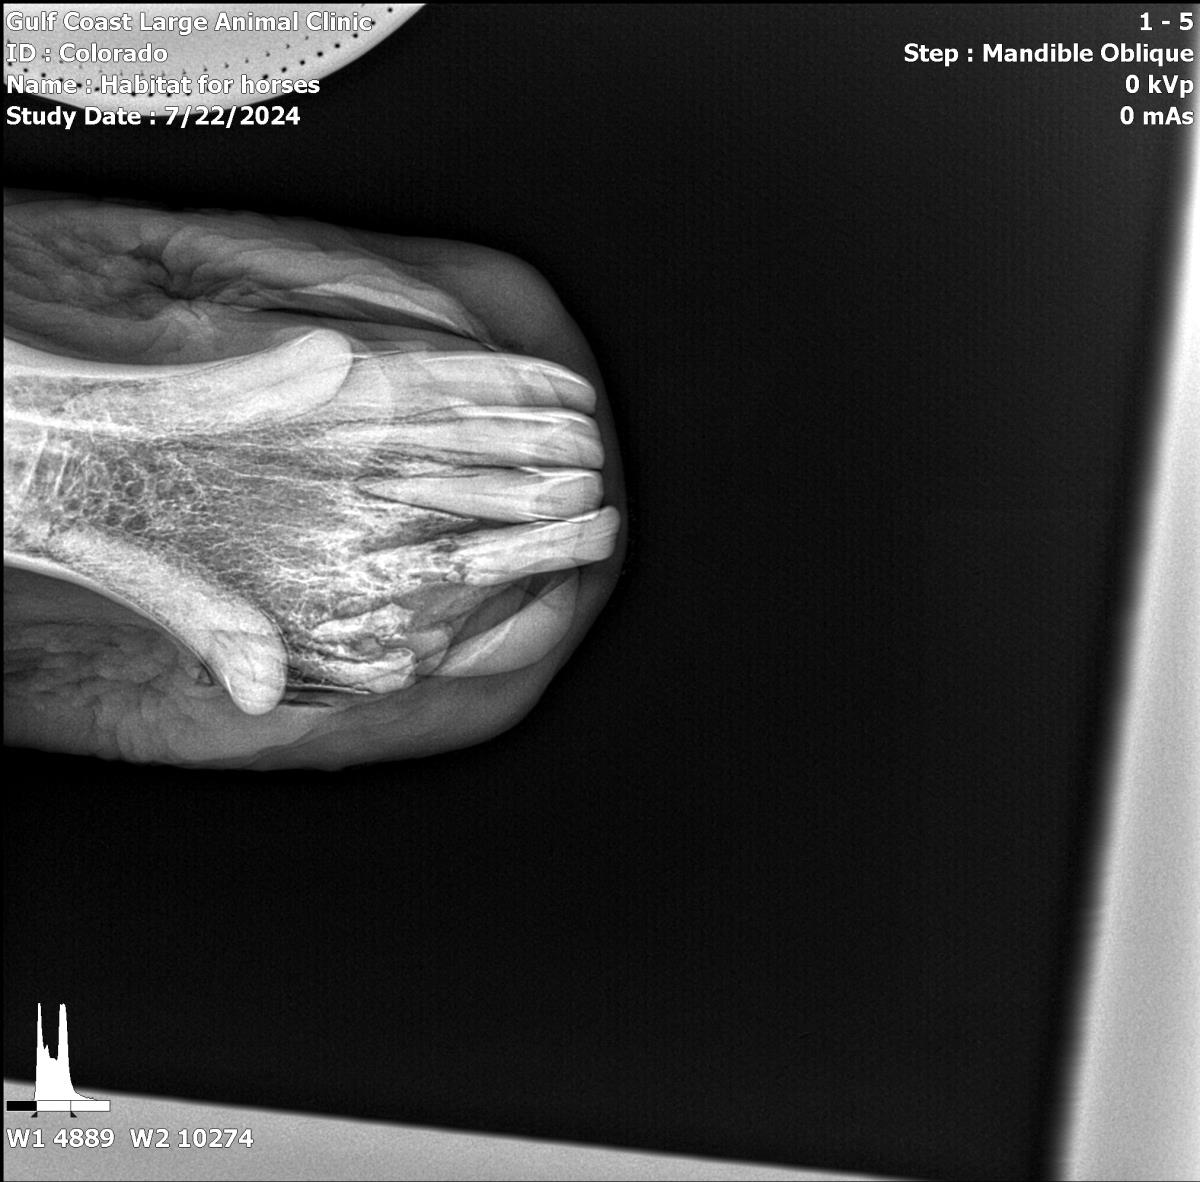

Pinto Colorado #21-010: Male Horse

Pinto Colorado

ID: 21-010 Horse

Breeds: Paint

Age: 22 years (approx.)